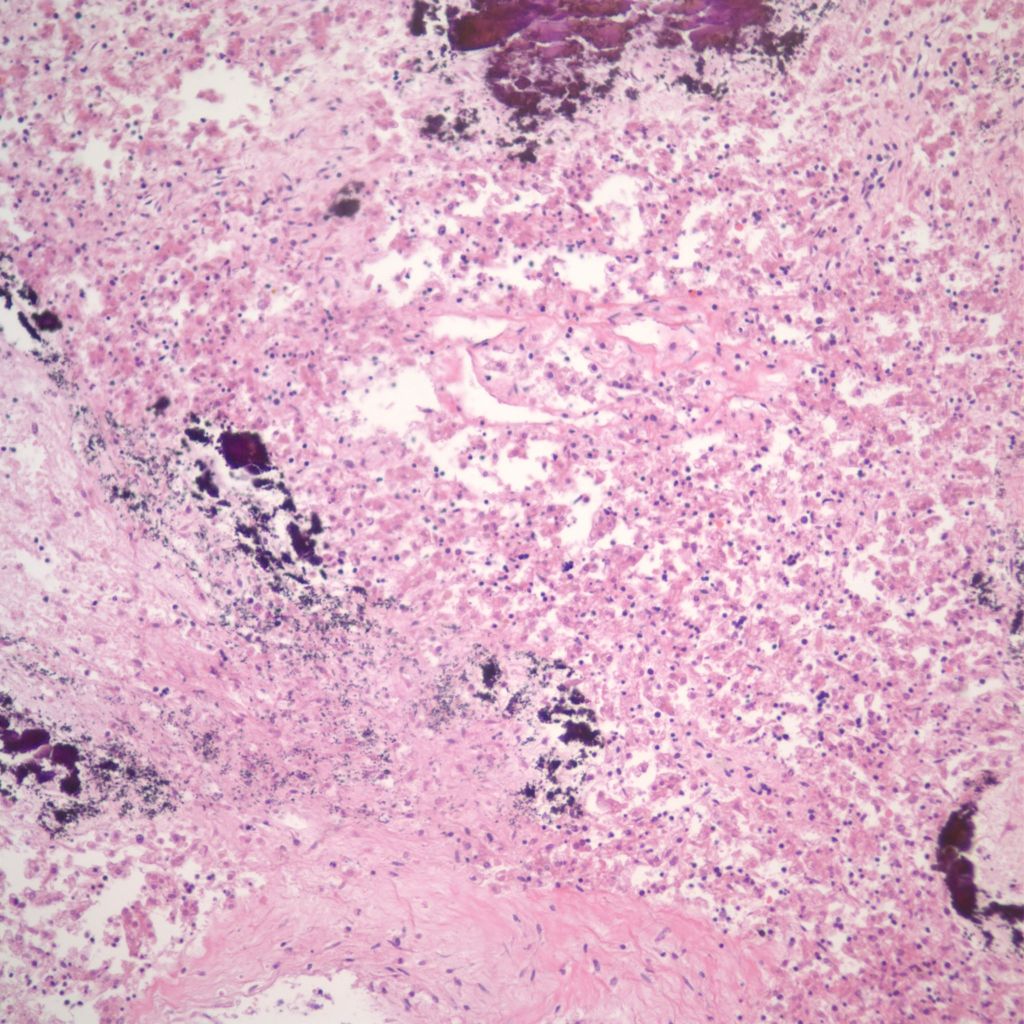

More cryptic in origin are focal subcapsular and periportal hemorrhages seen usually in early gestation fetuses that can be seen on fine grained postmortem radiographs (Fig 13a)9. These lesions may stain for both hemosiderin and calcium. (Fig 13b, c)